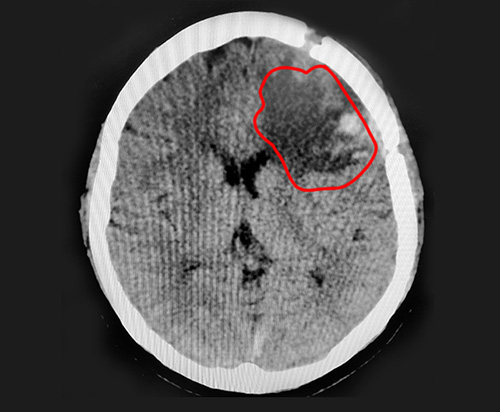

▲術(shù)后CT復(fù)查影像,巨大腦膜瘤已切除

術(shù)后CT復(fù)查影像中,巨大的腦膜瘤已被切除;颊邩(lè)觀開(kāi)朗的性格,也對(duì)其術(shù)后恢復(fù)起到了良好的推動(dòng)作用。